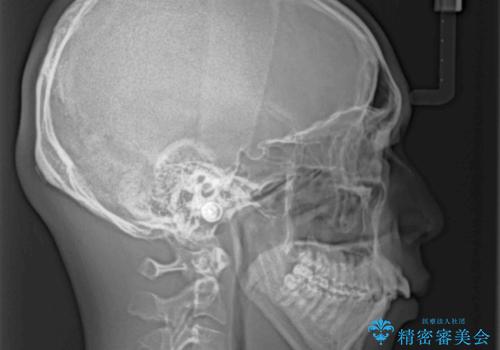

舌の突出癖などにより上顎前歯が前方に突出し、さらに歯列幅が狭小になっている状態でした。

また、上顎歯列全体が下顎に対して前方位に位置していました。

上顎歯列幅を側方に拡大するとともに、歯列全体を後方に移動させるためのアンカースクリューと補助装置を使用し、上顎左右第一小臼歯2本、下顎左右第二小臼歯2本、計4本を抜歯し、ワイヤー装置にて矯正治療を行うこととしました。